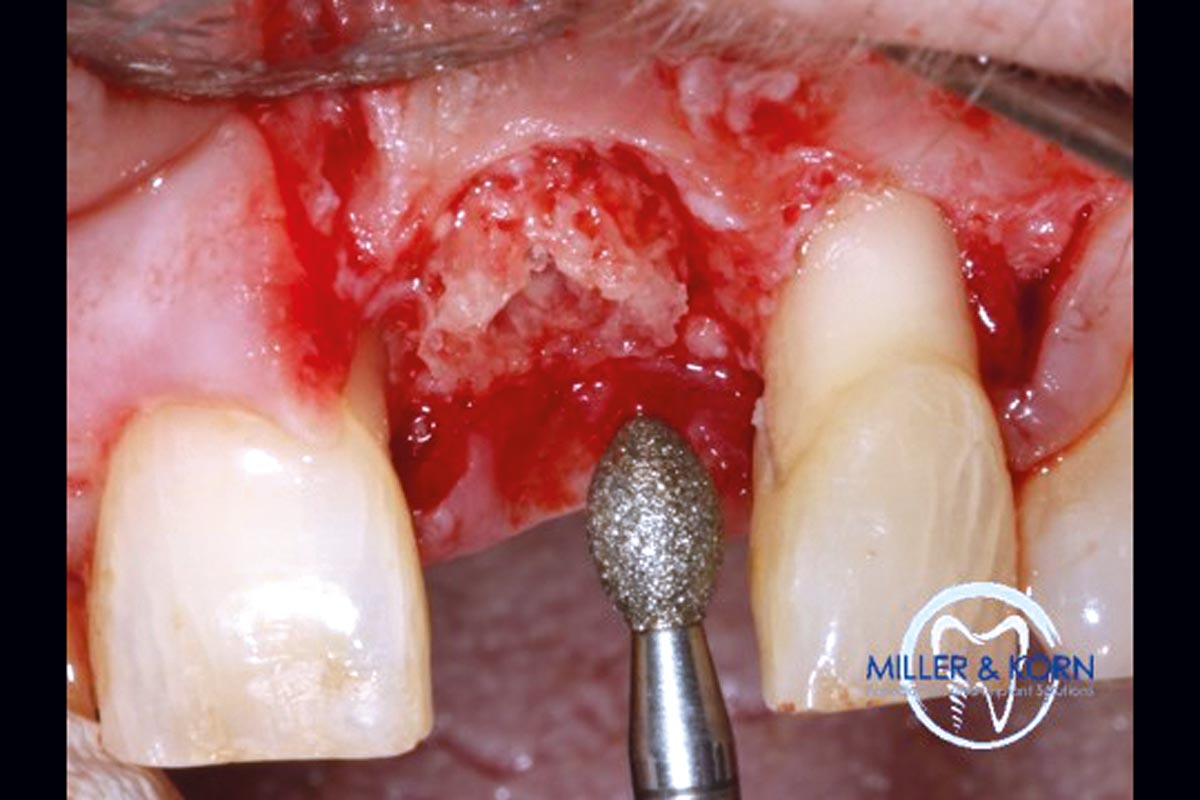

20/39 - Removal of sharp edges using a diamond tulipImmediate implant placement and correction of horizontal and vertical bone loss using an allograft bone ring, cerabone® and Jason® membrane - Drs. Miller and Korn